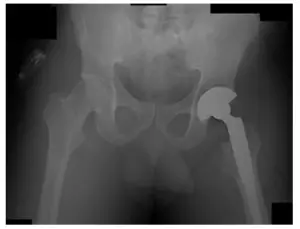

El paciente había hecho un seguimiento para revisar las radiografías. El paciente evoluciona favorablemente y se le realizará un seguimiento dentro de un año para controlar su ATC izquierda. El paciente está bien y no tiene dolor.

Radiografías de la THA izquierda. Las radiografías revelan que no hay fracturas y que la THA izquierda está bien alineada.